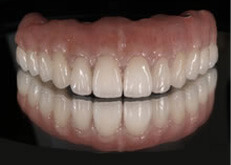

上部構造

インプラント治療を成功に導く為に必要不可欠な歯科技工。インプラント補綴は、特に技工士の技術が重要となる。オールオン4において、“口の中の見える部分”は全て歯科技工士の仕事なのです。当医院のオールオン4補綴はインプラント補綴で有名なノーベルバイオケア社公認インストラクター 志田和浩氏によるものです。本症例は、1歯1歯プロセラを装着した、オールオン4の上部構造としては最高級のものの一つです。